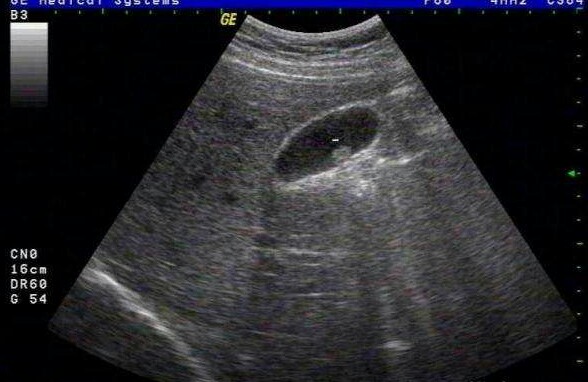

胆囊炎是胆道系统感染的常见病,其发病与胆汁淤滞、胆汁化学成分的改变、细菌感染有关,其中以细菌感染最常见。慢性胆囊炎可从急性胆囊炎迁延而来,也可继发于胆石症,也有相当一部分人无急性发作史,发现时即为慢性。胆囊炎常与胆石症互为因果,胆囊炎常诱发胆囊结石,胆囊结石又常促发胆囊炎。本病常发于20~40岁的青壮年,以女性多见。

胆囊炎可分为急性胆囊炎与慢性胆囊炎:

1.急性胆囊炎:发病急,有发热和右上腹阵发性绞痛,并向右肩放射,伴有恶心呕吐、食欲不振、腹胀、便秘等症状。当胆道梗阻引起化脓性感染时,可有黄疸、畏寒、高热等中毒症状,严重者可发生胆囊穿孔而引起急性腹膜炎。

2.慢性胆囊炎:与胆石症的症状相同,常有腹胀、上腹或右上腹不适.持续性钝痛、上腹灼热、 嗳气反酸等消化不良症状。当胆囊内浓稠粘液或结石进入总胆管引起梗阻时,可有典型的胆绞痛症状。吃煎炸食物或含脂肪多的食物,可诱发胆绞痛。